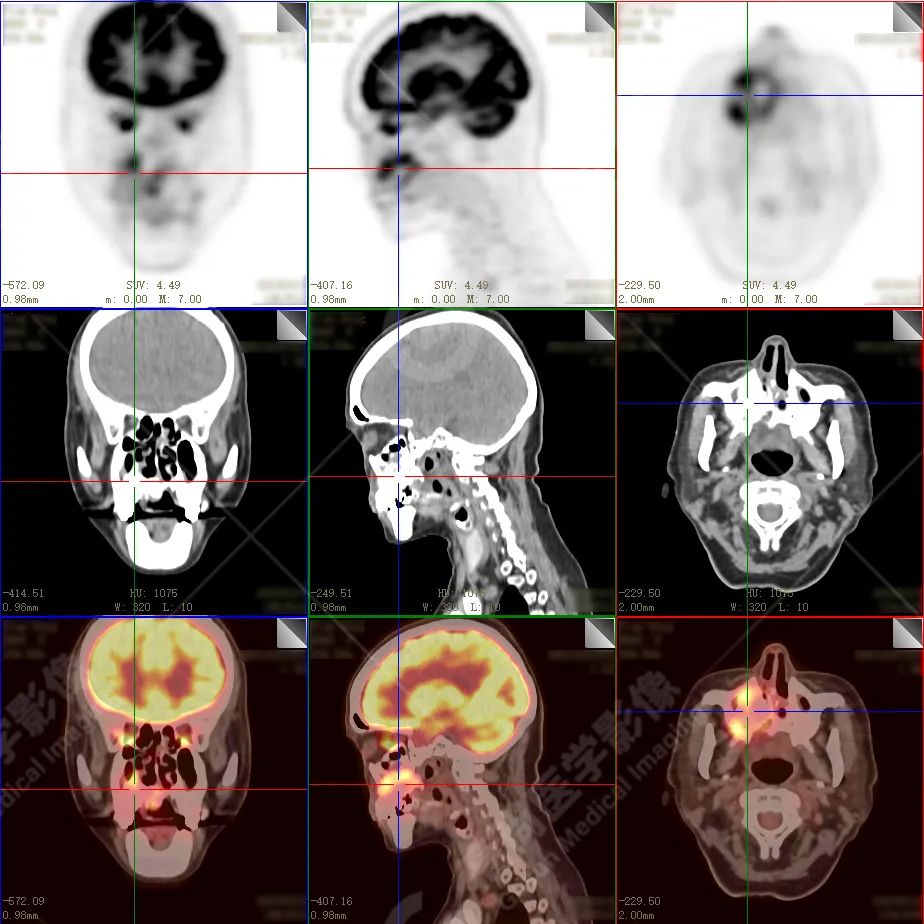

右侧上颌骨-上颌窦骨壁-骨性鼻中隔区域见片块状放射性摄取异常增高影,最大层面约 4.1 cm×3.8 cm×2.8 cm,SUV 最大值为 10.4,CT 示上述部位见成骨性改变,骨质不均匀弥漫性增厚、密度不均匀增高,并可见肿瘤骨影,边缘毛糙,周围伴软组织增厚。

根治性手术在放疗后骨肉瘤的治疗中是必须的,然而根治性手术仅仅适用于早期的病例,如本例病人,相对早期,周围组织结构无明显侵犯,PET 示肿瘤代谢也局限于肿瘤本体。